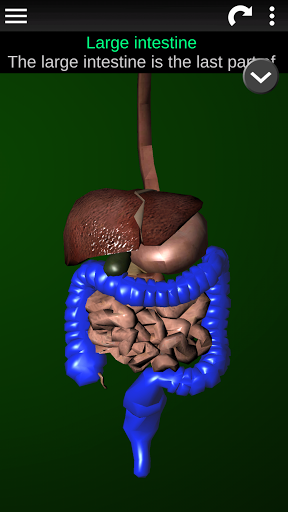

* Spijsverteringsstelsel, inclusief de maag, dunne darm, dikke darm, en een animatie van dit systeem.

* Gemakkelijk te openen en te navigeren (zoom, 3D-rotatie).

* Beschrijvingen van elk orgel.

Deze app is ontworpen als aanvulling op de studie van anatomie in verschillende onderwijs-, gezondheidszorg- en culturele omgevingen.